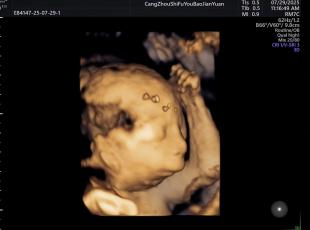

给宝宝的“立体影像”,让产检更安心

科室采用三维/四维超声技术开展胎儿检查,能清晰呈现胎儿面部及身体关键结构的影像,让准父母直观感受宝宝的发育状态。检查中,医生会借助技术对唇腭裂、小下颌等结构异常进行细致观察,同时基于三维容积数据,从多个平面评估胎儿心脏、大脑、脊柱等重要部位,为孕期健康管理提供专业参考。

正常胎儿面部三维照片